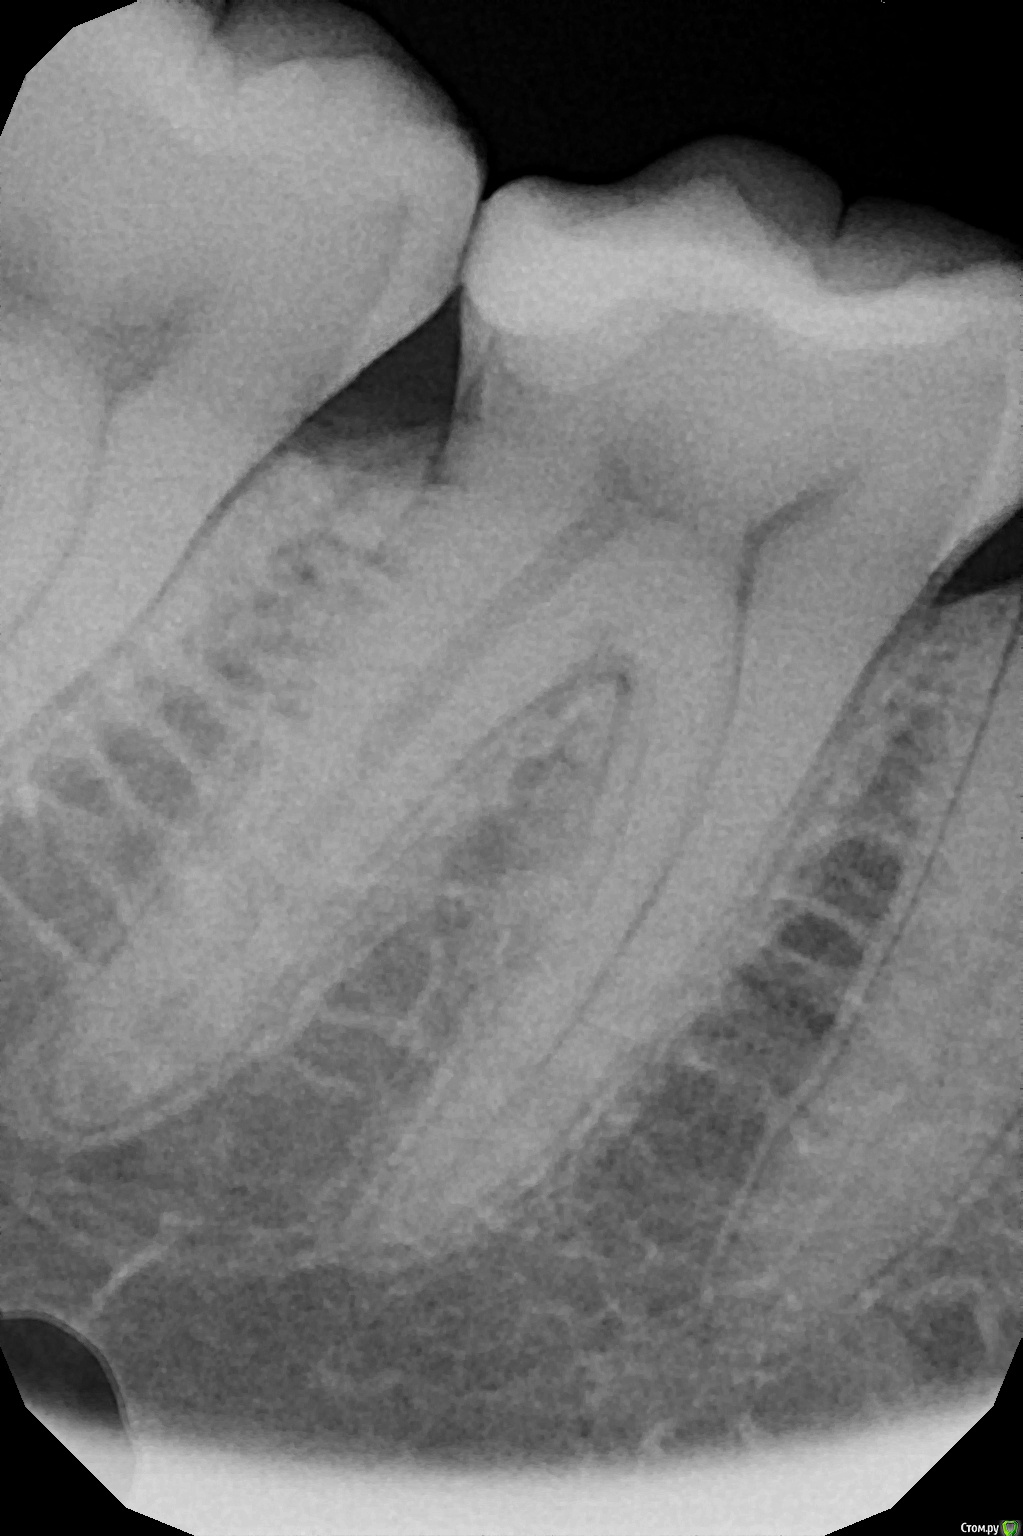

Здравствуйте! Год назад у меня откололся кусок пломбы от 6-ого зуба справа внизу. Стала забиваться пища, появились болевые ощущения. Пломбу мне поменяли, но боль не прошла. В течение двух недель сохранялся постоянный дискомфорт, спустя это время остались боль при накусывании и реакция на холодное/горячее. Кушала долгое время только на левой стороне. Плюс периодическая ноющая боль наверху над этим зубом, в каком конкретном зубе болит определить не могу - боль по всей стороне.

Полгода назад был пролечен кариес на соседнем зубе, седьмом. Стоит небольшая пломба.

За этот год положительная динамика есть - я могу жевать на правой стороне, правда не очень твердую пищу. Иногда зубы не беспокоят совсем. Но тем не менее очень часто та ноющая боль возвращается. Ночью она спать не мешает, но отнимает много сил. На кислое-холодное реагирует пломба 6-ого зуба, реакция кратковременная.

Прикрепляю общий снимок и прицельный снимок шестерки. Есть КТ этой стороны, если нужно.

Я думаю, проблема у вас все-таки в 6-ом зубе. Скорее всего в нем имеется хроническое воспаление пульпы. Процесс вялотекущий, поэтому сильных болей вы не испытываете. Для подтверждения диагноза нужно сделать ЭОД. На втором месте по вероятности стоит нарушение герметичности либо микроотрыв пломбы. Решается заменой реставрации. Наличие длительной ноющей боли вверху без четкой локализации является скорее всего иррадиацией от нижнего зуба. Это тоже говорит о том, что скорее всего в 6-ом зубе пульпит.